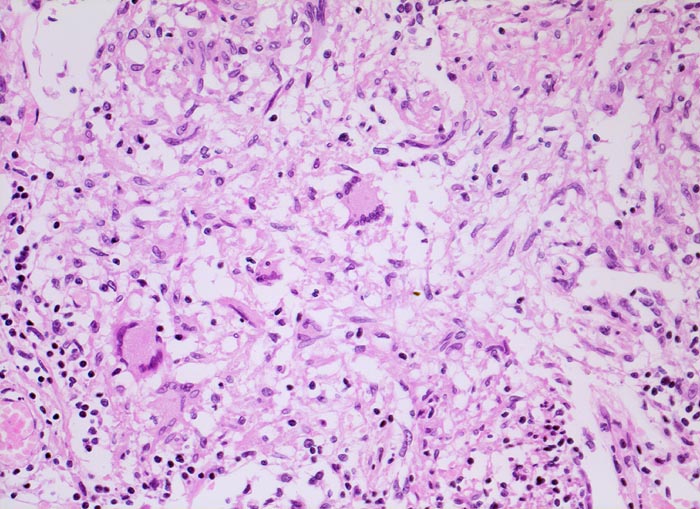

Tuberkulosegranulom

Lunge

Schlanke spindelige Epitheloidzellen und einzelne Riesenzellen vom Langhanstyp mit peripher hufeisenförmig angeordneten Kernen. Am Rand kleine Lymphozyten.

Die Epitheloidzellen in einem Tuberkulosegranulom sind in der Regel schlank. Die Epitheloidzelle des Sarkoidosegranuloms haben mehr Zytoplasma und plumpere Kerne. Verkäsende Nekrosen kommen allerdings auch bei Sarkoidosegranulomen vor. Vrgl. PathoPic ID 4042